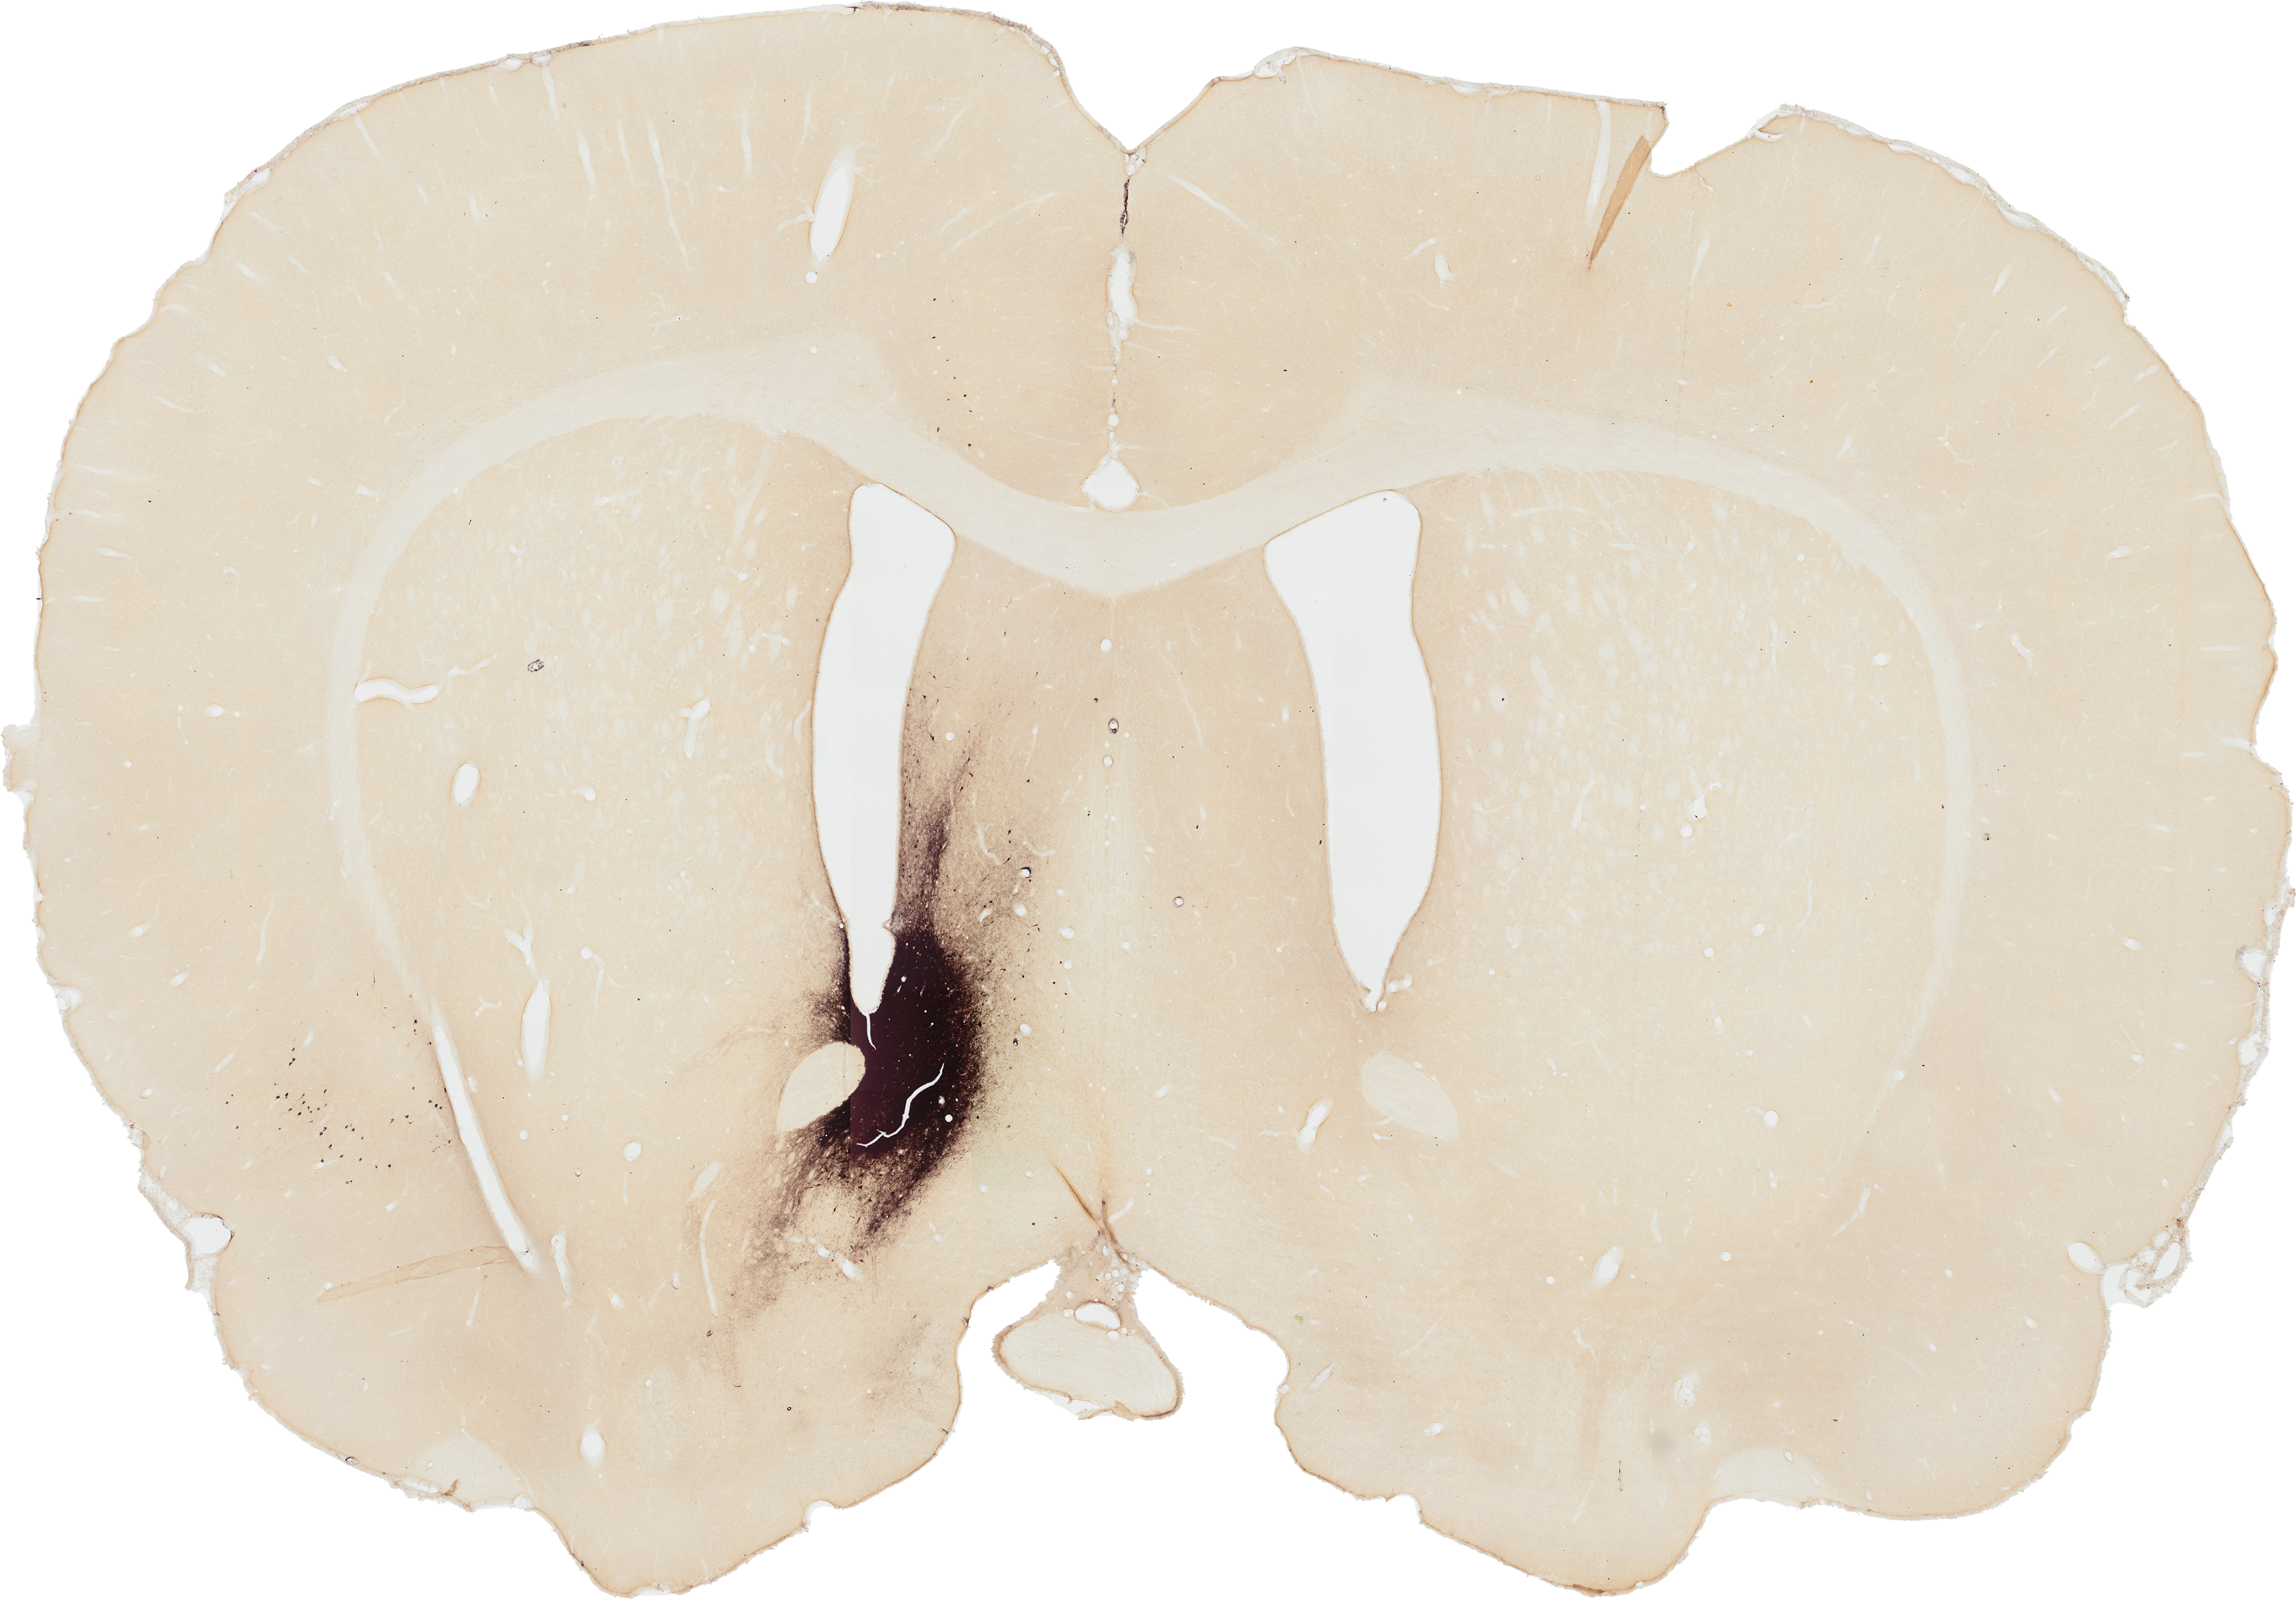

STAIN THE BRAIN

Welcome to Stain the Brain!

Learn more about the connections in the brain and the tracing methods that are used to visualize these connections.